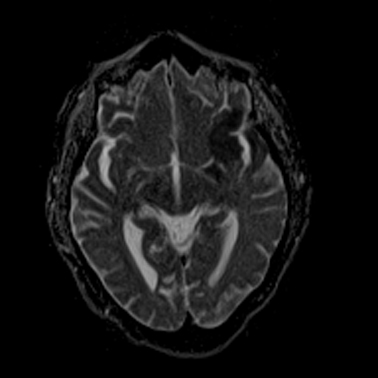

MRT des Nervensystems (Neuroradiologie)

Aufgrund der guten Gewebedifferenzierung verwenden wir die Kernspintomographie (MRT) in der Neuroradiologie zur Untersuchung von Gehirn, Gesicht und Augen sowie von Wirbelsäule und Rückenmark. Schlaganfälle lassen sich postakut minutenschnell lokalisieren und auf ihre Ursache hin untersuchen. Winzige Tumoren, Hirnabbauprozesse, Gefäßmissbildungen, Enzephalitiden (Gehirnentzündungen), Anfallsursachen (Epilepsie) oder Unfallfolgeschäden können gut differenziert werden.

Da die Magnetresonanz nicht nur Schnittbilder (Tomographien), sondern auch Spektren (Energieverteilungen) liefert, lassen sich mit der MR-Spektroskopie Stoffwechselprodukte im Gehirn lokalisieren und mengenmäßig erfassen und somit auch Gehirnaktivitäten qualitativ und quantitativ nachweisen.

Schlaganfall 1

Schlaganfall 2